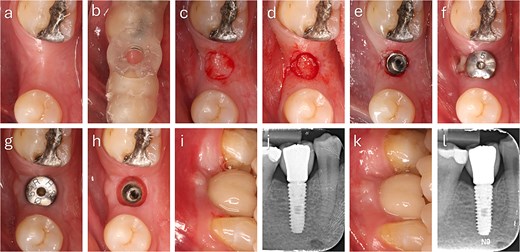

For immediate loading, digital scans were obtained before graft placement to ensure accuracy; in delayed loading, scans were performed at two months, confirming improved buccal tissue thickness and stability prior to definitive restoration (Fig. 4).

Quantitative digital evaluation of buccal mucosal thickness before and after graft healing. Superimposed STL models show the pre-grafting surface and the 2-month postoperative surface after alignment in DentalCAD 3.1 (exocad, Germany). Linear measurement taken at the widest buccal contour demonstrates an increase in mucosal thickness of ~1.49 mm between the two time points.